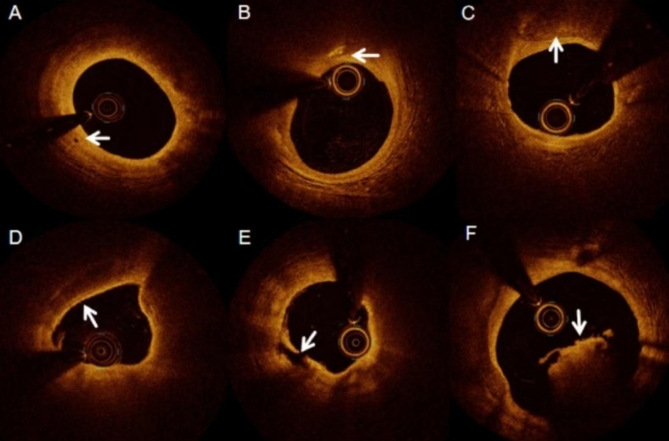

非阻塞性冠状动脉心肌梗死(MINOCA)是一种异质性疾病,具有不同的病理生理机制和预后。近年来发现MINOCA的主要心血管不良事件发生率与心肌梗死合并冠状动脉疾病(MI-CAD)发生率相似,两者的发病机制难以通过冠状动脉造影(CAG)明确。因此,本研究的目的是通过光学相干断层扫描(OCT)研究MINOCA和MI-CAD患者的临床特征、斑块特征和预后。回顾性分析553例经CAG和OCT检查的AMI患者的罪魁祸首病变。随后将患者分为两组:MINOCA组和MI-CAD组。比较两组患者的临床特点、斑块特征及预后。主要终点定义为主要心脏不良事件(MACE)的综合,包括心源性死亡、非致死性心肌梗死、靶病变血运重建术、卒中以及因心绞痛或心力衰竭再次住院。(1)与MI-CAD患者相比,MINOCA患者st段抬高型心肌梗死(STEMI)发生率较低,联合药物洗脱支架(DES)史较少。此外,他们还表现出较低的低密度脂蛋白胆固醇(LDL-C)、总胆固醇(TC)、甘油三酯(TG)、肌钙蛋白T (TnT峰值)和肌酸激酶(CK峰值)水平。MINOCA组左前降支(LAD)病变较多,左旋支(LCX)病变较少。此外,与DES相比,他们显示出更低的多支血管病变患病率,出院后阿司匹林、P2Y12受体抑制剂、β受体阻滞剂、血管紧张素转换酶抑制剂/血管紧张素受体阻滞剂(ACEI/ARBs)的使用减少,以及更高比例的保守治疗。MINOCA组血栓发生率低于MI-CAD组,差异有统计学意义(P < 0.05)。与MI-CAD患者相比,MINOCA患者在OCT上有更少的高危斑块,更有可能接受保守治疗,支架置入率更低,出院后药物治疗更少。两组在30天和1年的MACE发生率相似,突出了个体化治疗对MINOCA患者的重要性。发生MACE的MINOCA患者更有可能表现出高风险的OCT斑块特征,巨噬细胞浸润被认为是一个独立的危险因素。OCT斑块特征如斑块破裂、斑块糜烂、胆固醇结晶、巨噬细胞、微血管、TCFA等可能在两组患者的进展中发挥了不同的作用。

Myocardial infarction with nonobstructive coronary artery (MINOCA) is a heterogeneous disease with different pathophysiological mechanisms and prognosis. In recent years, it has been found that the incidence of major cardiovascular adverse events in MINOCA is similar to that of myocardial infarction with coronary artery disease (MI-CAD), and it is difficult to clarify the pathogenesis of both through coronary angiography (CAG). Therefore, the aim of this study is to investigate the clinical features, plaque characteristics and prognosis of patients with MINOCA and MI-CAD through optical coherence tomography (OCT). A total of 553 culprit lesions from AMI patients who underwent CAG and OCT were retrospectively analysed. Patients were subsequently divided into two groups: the MINOCA group and the MI-CAD group. The clinical characteristics, plaque characteristics and prognosis of the two groups were compared. The primary endpoint was defined as a composite of major adverse cardiac events (MACE), including cardiac death, non-fatal myocardial infarction, target lesion revascularization, stroke, and rehospitalisation for angina or heart failure. (1) Patients with MINOCA exhibited a lower incidence of ST-segment elevated myocardial infarction (STEMI) and a less frequent history of combined drug-eluting stent (DES) compared to those with MI-CAD. Additionally, they demonstrated lower levels of low density lipoprotein cholesterol (LDL-C), total cholesterol (TC), triglycerides (TG), peak troponin T (peak TnT) and peak creatine kinase (peak CK). The MINOCA group had more lesions in the left anterior descending (LAD) and fewer in the left circumflex (LCX). Additionally, they demonstrated a lower prevalence of multibranch vasculopathy and a diminished post-discharge use of aspirin, P2Y12 receptor inhibitors, beta-blockers, angiotensin converting enzyme inhibitor/angiotensin receptor blockers (ACEI/ARBs), and a higher proportion of conservative treatment compared to DES. The frequency of plaque rupture, calcified plaque, cholesterol crystals, macrophages infiltration, microvessels, thin-cap fibroatheroma (TCFA), and thrombus were found to be lower in the MINOCA group than in the MI-CAD group, with these differences being statistically significant (P < 0.05); (2) No significant difference was observed in the incidence of MACE at 30-days and 1 year between patients in the MINOCA and MI-CAD groups (P > 0.05). Compared with MI-CAD patients, MINOCA patients had fewer high-risk plaques on OCT and were more likely to be treated conservatively, with lower rates of stenting and less post-discharge pharmacological treatment. Both groups had similar rates of MACE at 30-day and 1 year, highlighting the importance of individualising treatment for MINOCA patients. Patients with MINOCA who develop MACE are more likely to exhibit high-risk OCT plaque features, with macrophage infiltration identified as an independent risk factor. OCT plaque features such as plaque rupture, plaque erosion, cholesterol crystals, macrophages, microvessels, TCFA may have played different roles in the progression of the two groups of patients.